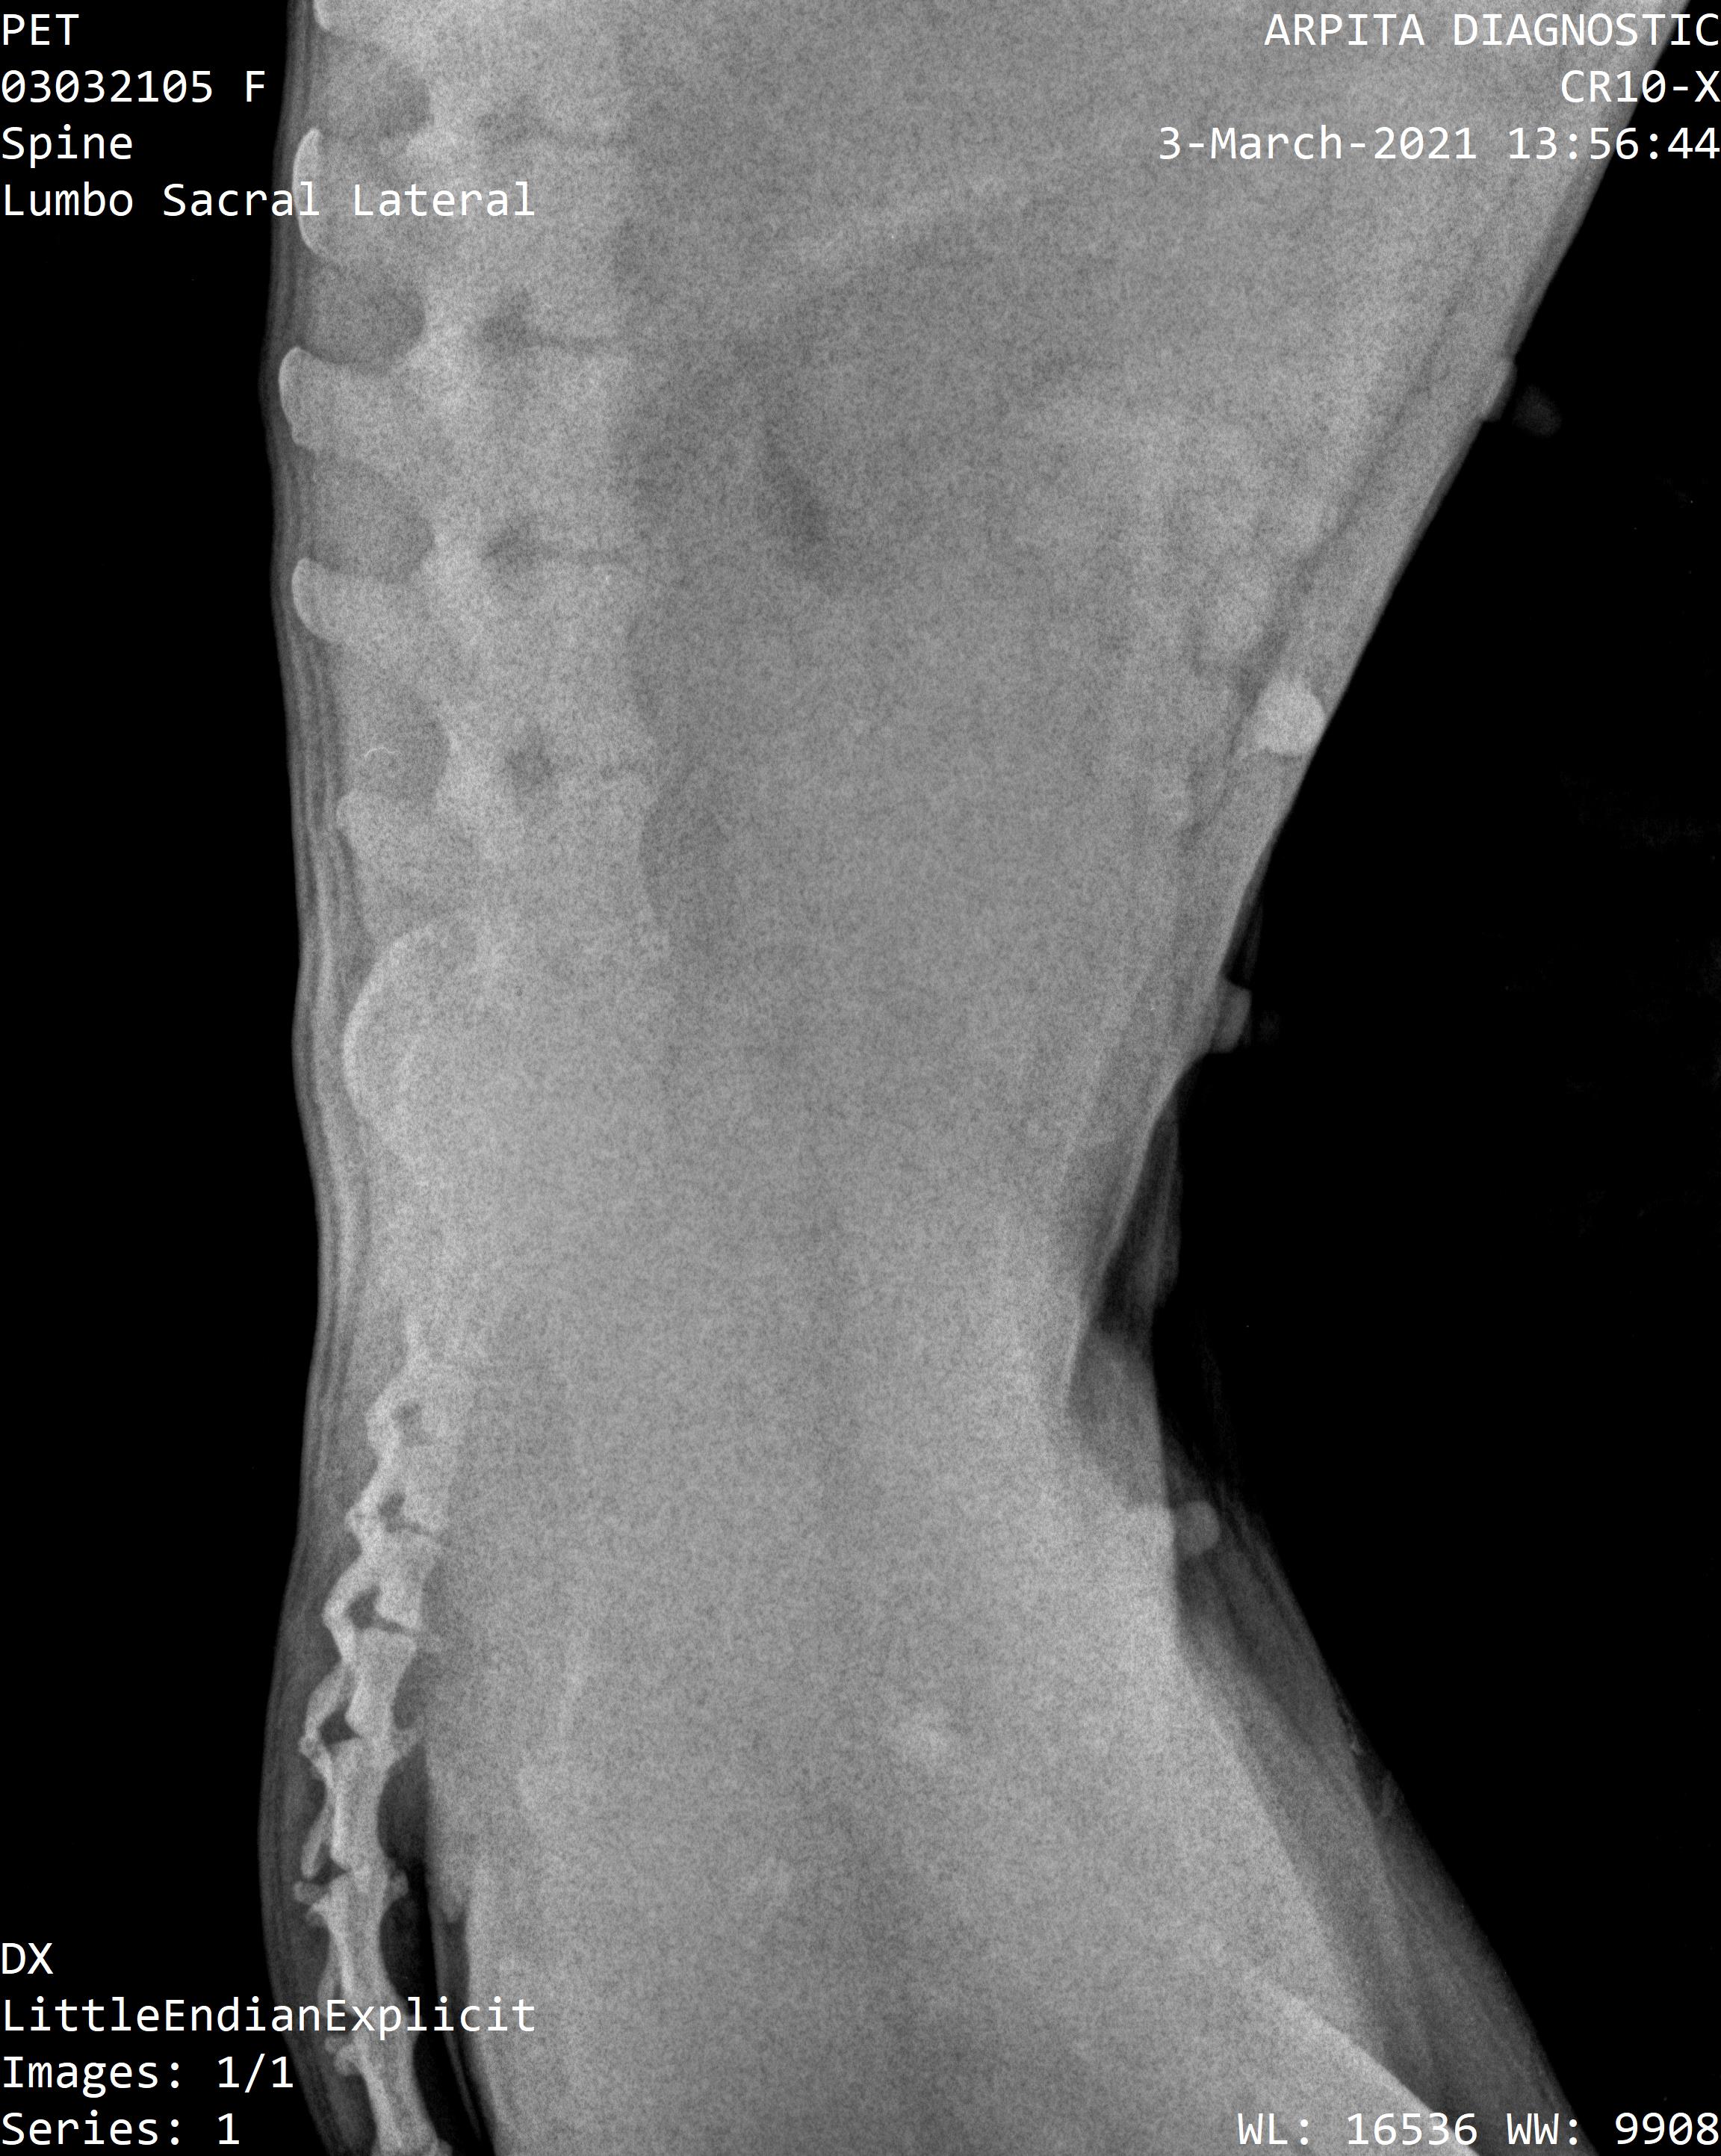

We got Zoeys x-rays done and the vets mentioned she will need extensive treatment and looking after for a few months.